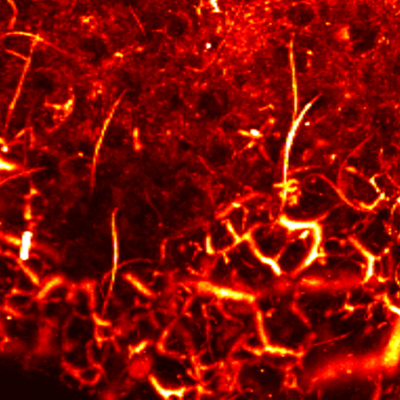

Layer by layer visualization of subdermal microvessels and pigments

MAP